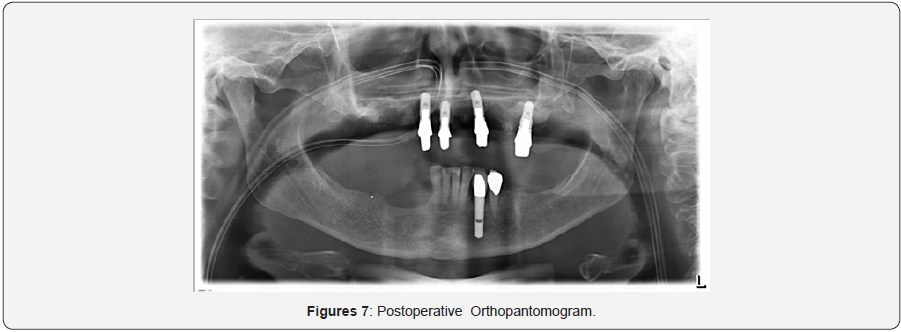

The proposed therapy option for a rhinosinusitis caused by foreign body reaction is the surgical revision of the sinus but with the necessity of implant removal remaining still controversial [15,16]. The most indicated technique for the revision is FESS (Functional Endoscopic Sinus Surgery), which is favored over Caldwell-Luc because, is less invasive offering same results. In our case through a severe periimplantitis with chronic pain and infection of the whole maxillary sinus we decided to perform a more radical surgery, including the removal of the located implants in the regions 15 and 17 for avoiding a relapse.